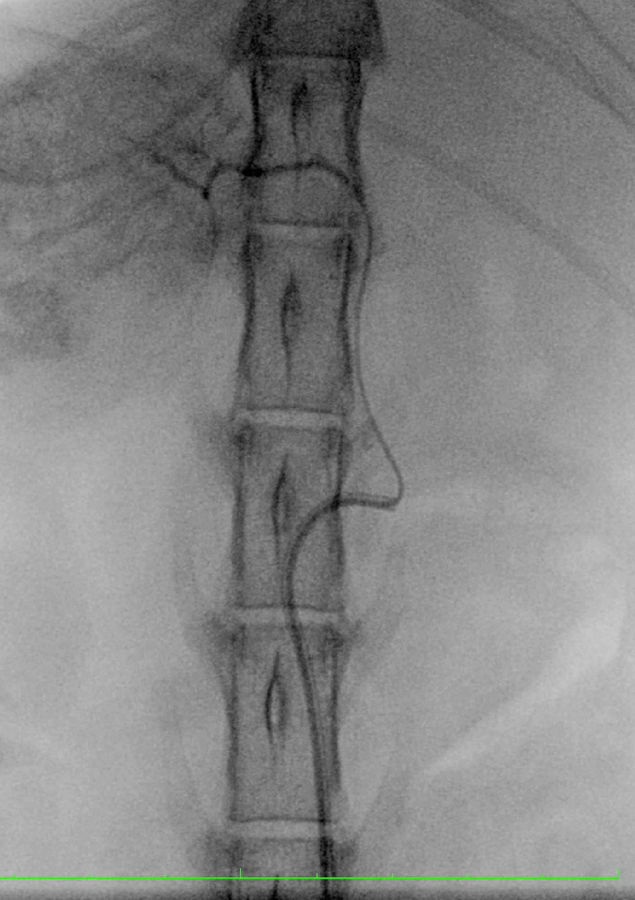

【実施症例】腰下リンパ節に転移した血管肉腫に対する動注療法

腰下リンパ節に転移した血管肉腫。

腫瘍の頭側の腹大動脈にリザーバーを設置し、抗がん剤の投与を行った。腫瘍は1/3以下に縮小が認められた。

血管肉腫が転移した腰下リンパ節

腫瘍陰影(DSA画像)

実施前

実施後